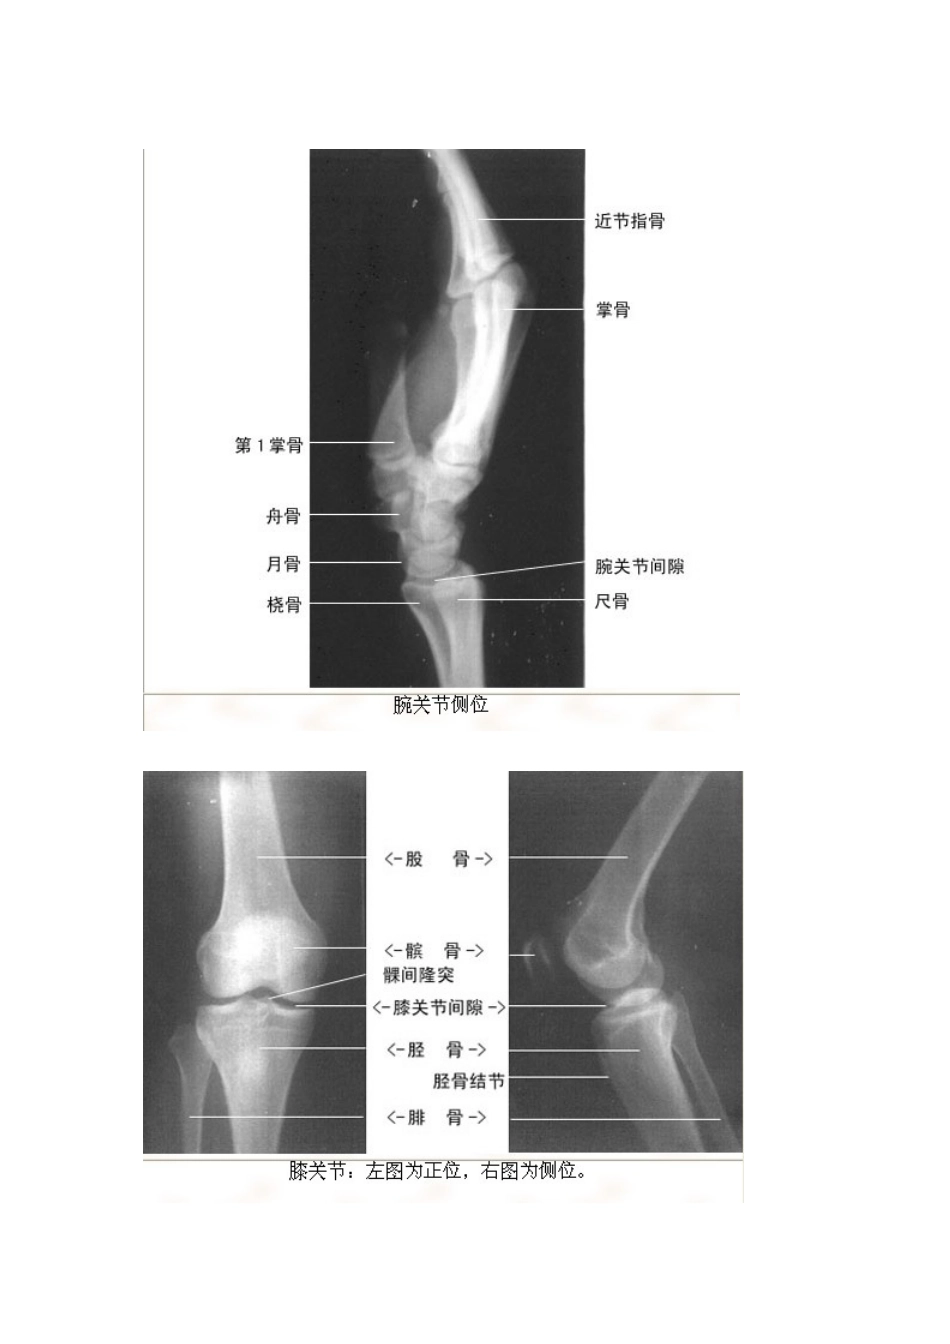

影像解剖珍藏版VIP免费